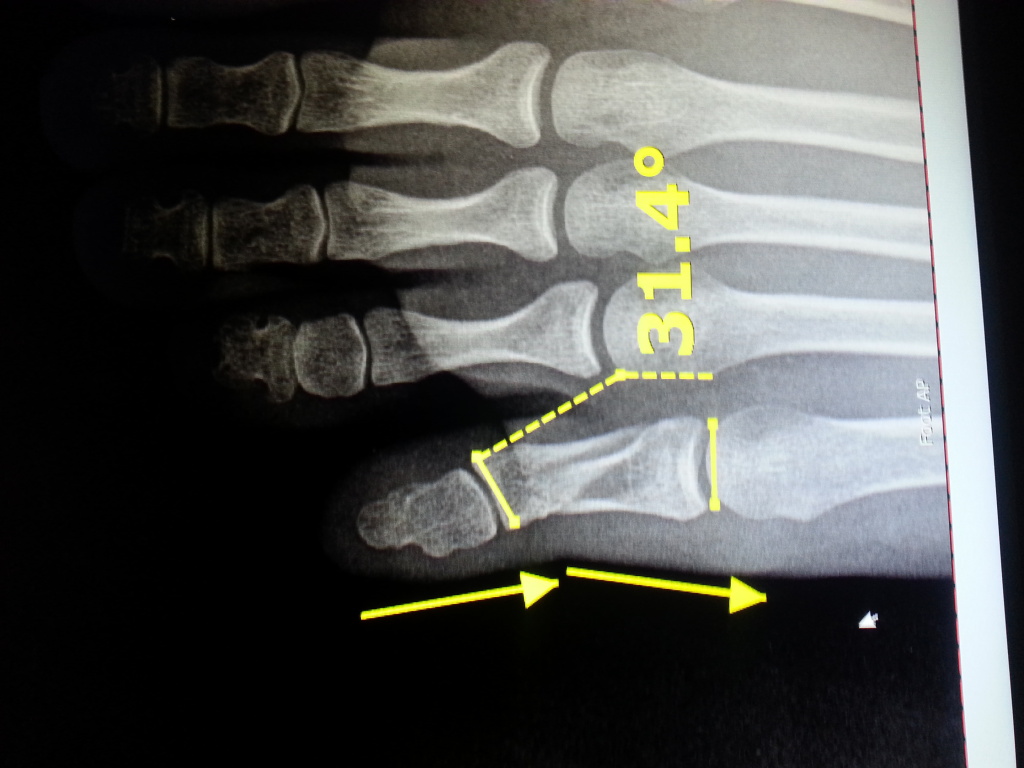

Image Comminuted Fracture of the Great Toe MSD Manual Professional

Image Comminuted Fracture of the Great Toe MSD Manual Professional Crush Fracture Big Toe When to see a doctor for a broken toe. While these bones are small, a broken toe can. Even though toes are small, injuries to the toes can often be quite painful. Phalangeal fractures are the most common foot fracture in children. Web an injured great toe is a common injury, usually caused by dropping a heavy object on the. Crush Fracture Big Toe.